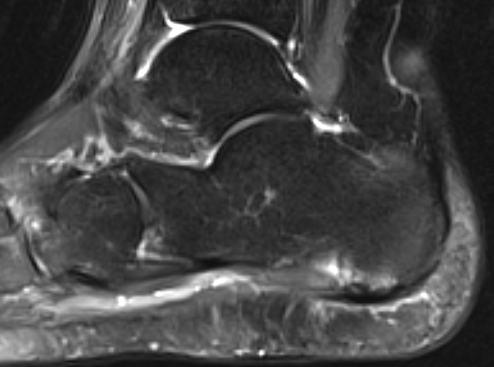

MRI

Thickened plantar fascia with tears

Exclude - retrocalcaneal bursitis / calcaneal stress fracture / Baxter's neuroma / tarsal tunnel syndrome